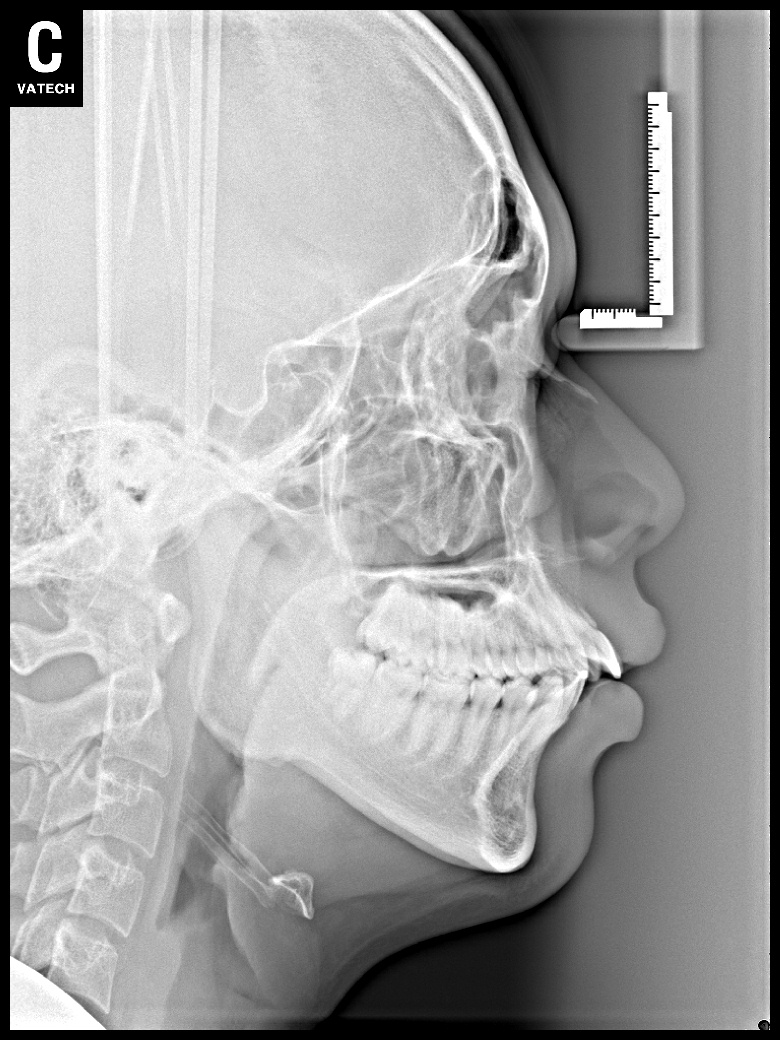

치료 후 사진입니다.